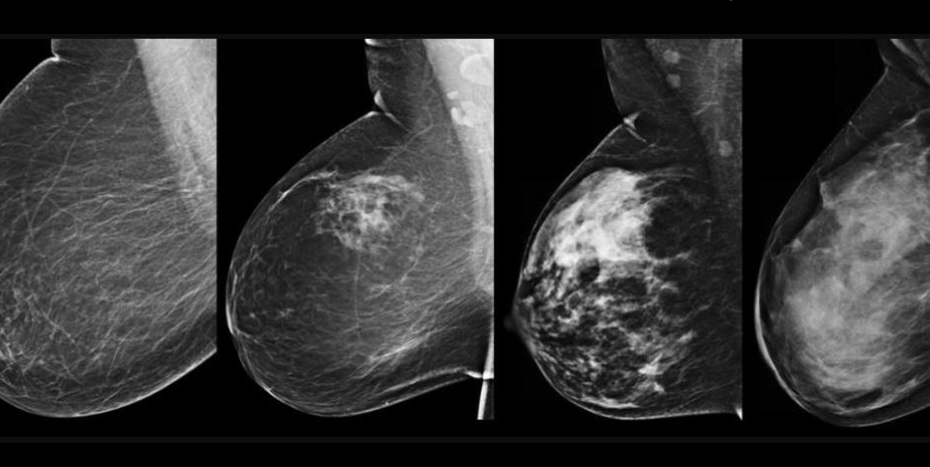

Guide: Breast tomosynthesis, or 3D mammography, is a breast imaging procedure in which an X-ray moves in an arc over the breasts as the imaging specialist compresses the breasts to… Read More »Is A 3D Mammogram Better Than A Regular Mammogram?